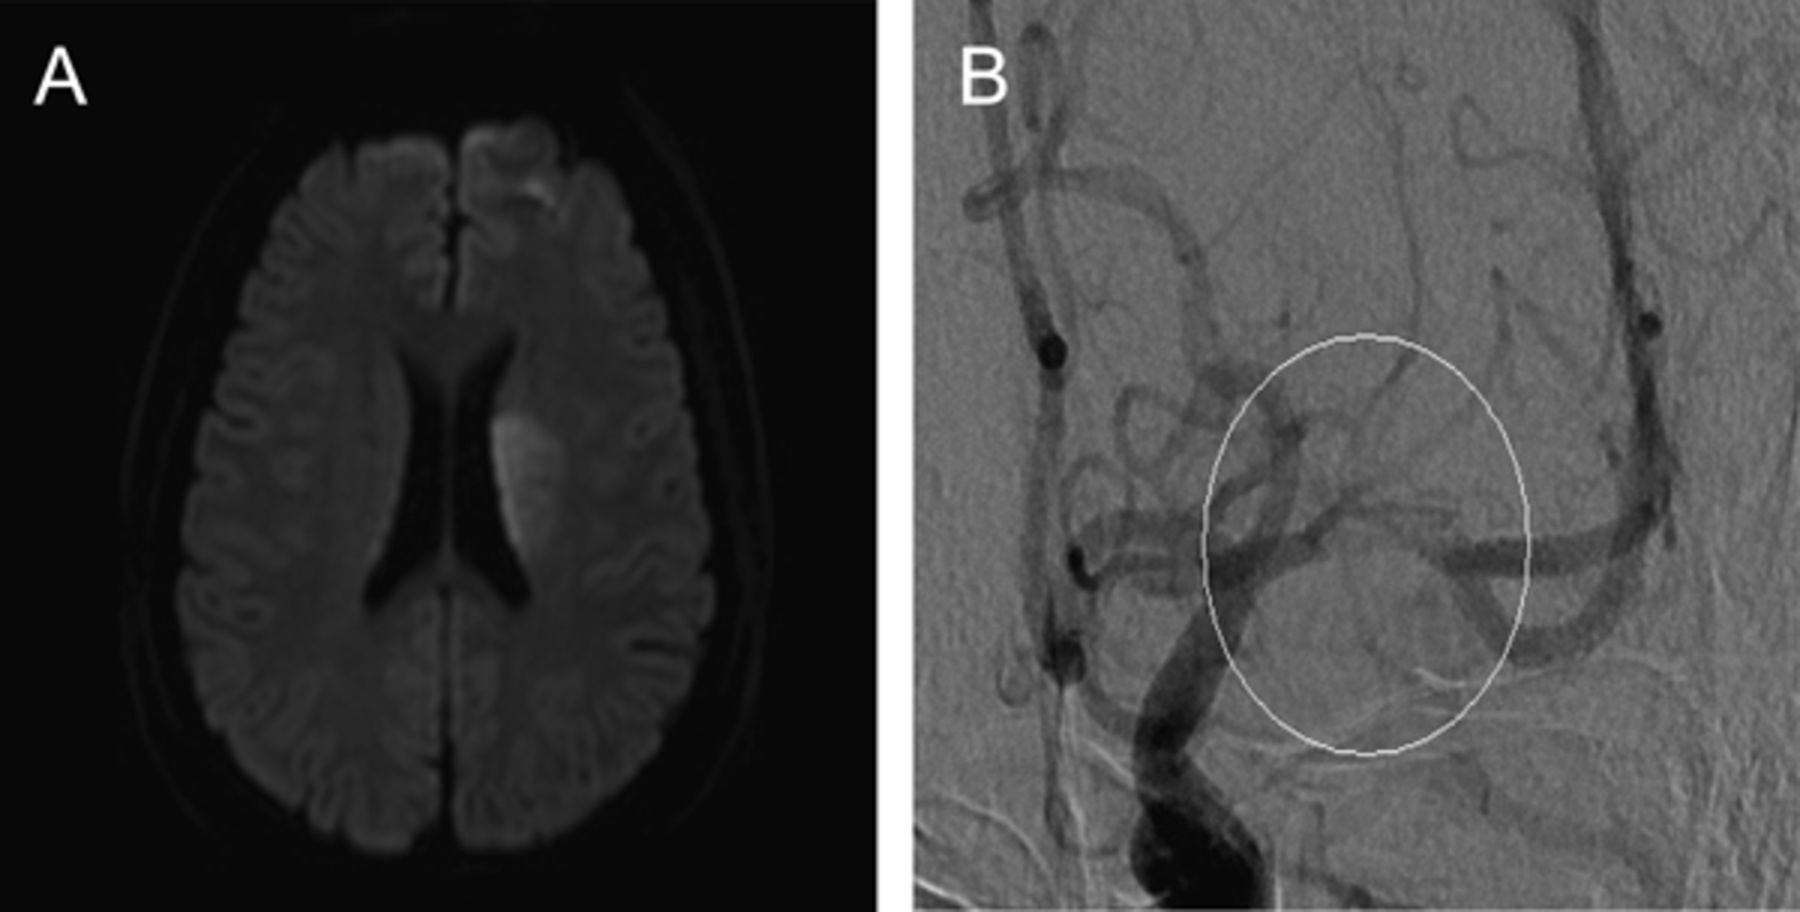

一个29岁的男人面对单边轻微的头痛3天,类似于以前的头痛,但与进行性加重;没有前期感染或创伤。MRI显示左striatocapsular梗死(图1一个),没有证据表明cardioembolism或血管炎。数字减影血管造影显示左大脑中动脉(MCA)狭窄的树干(图1 b)。校内的血肿显示动脉解剖。1膨胀的校内的血肿在T2 *与一个古怪的高信号边缘上矢状t1加权成像,沿着前上的MCA动脉穿支的起源(墙图2)。诊断是自发MCA解剖。

图2

影子从校内血肿迹象

低信号强度(箭头),在左边M1树干在T2 *图像(“影子标志”)和高信号边缘(B,空心箭头)的中期部分左大脑中动脉在矢状高分辨率t1加权图像。